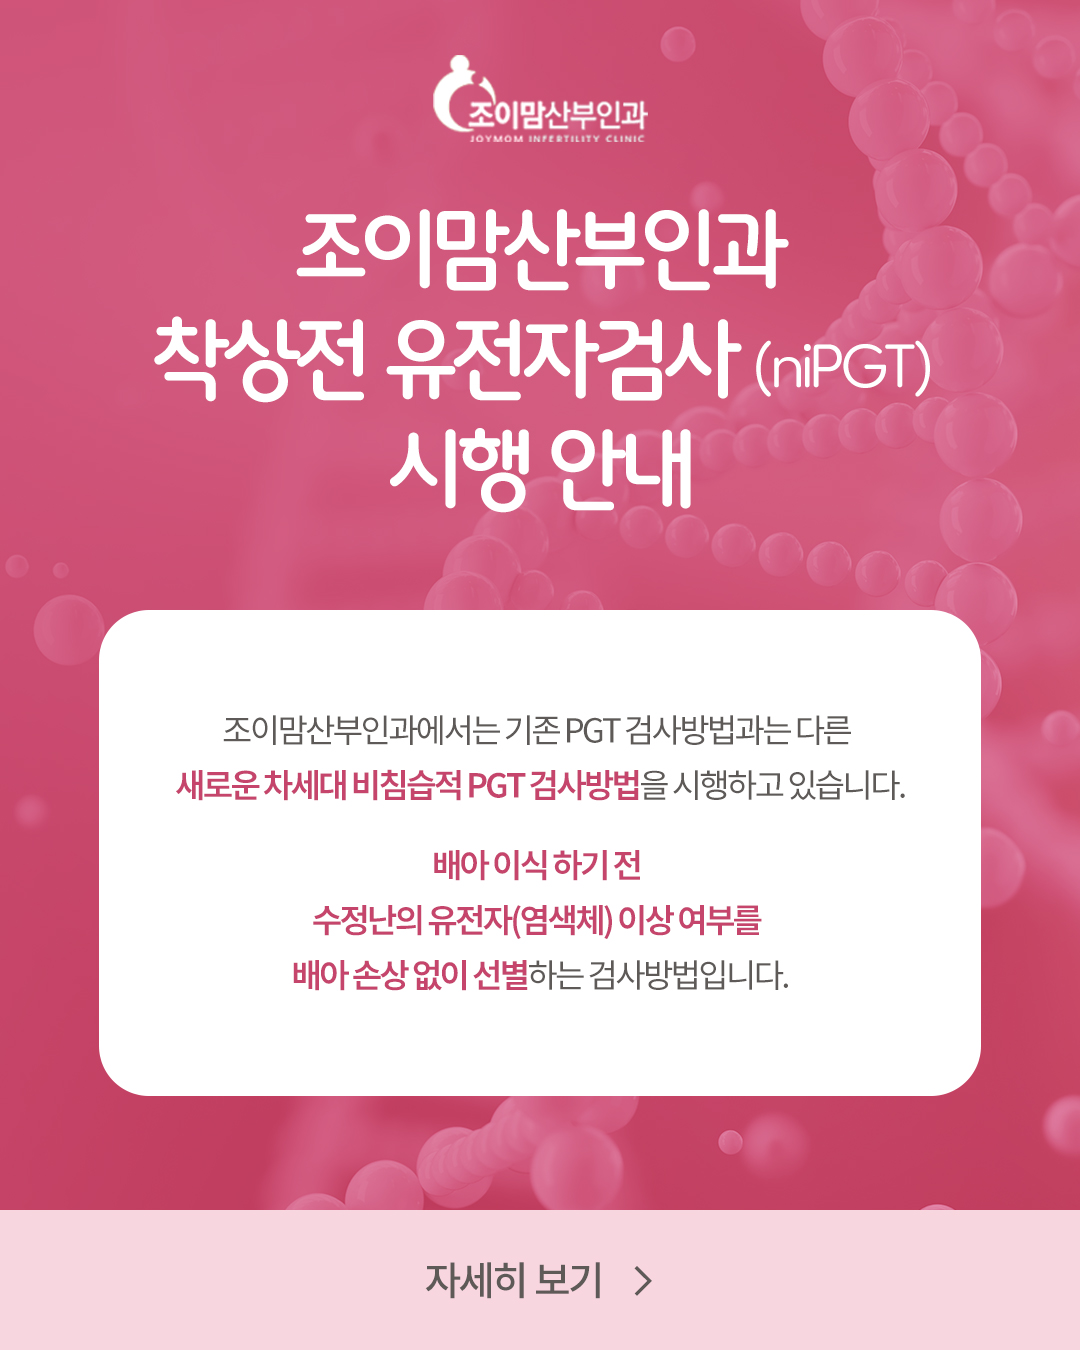

niPGT(차세대 비침습적

착상전 유전자검사) 가능 -